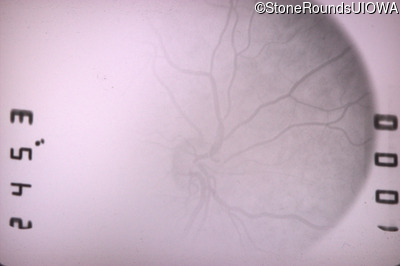

Infrared Fundus Photograph - Right - 20/40 -1

Exemplar